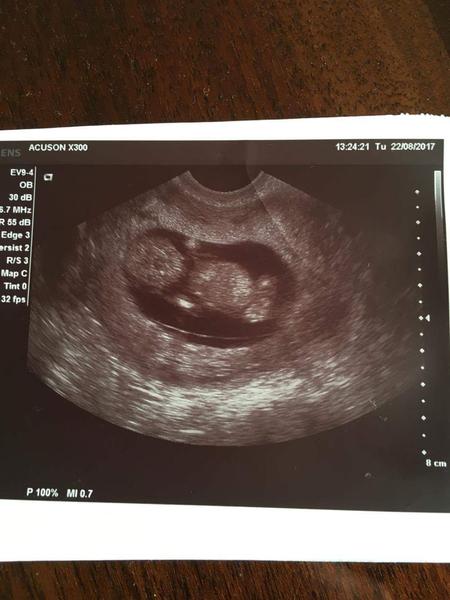

Ahojky jsme tu nová a hned s panikařícím dotazem 🙂 jsem v 5tt - váček byl v uterý potvrzen Dr. (nebyla jsme si jistá zda už jsem nebyla těhotná v minulém cyklu, proto si mě vzala tak brzo) a za dva týdny mám dorazit na srdíčko. Cca před týdnem mi přišly bolesti jako před MS takže jsem nejdřív neměla ani podezření že jsme těhotná. A od včera najednou už nic. Za pozitivní i ty negativní zkušenosti děkuji 🙂